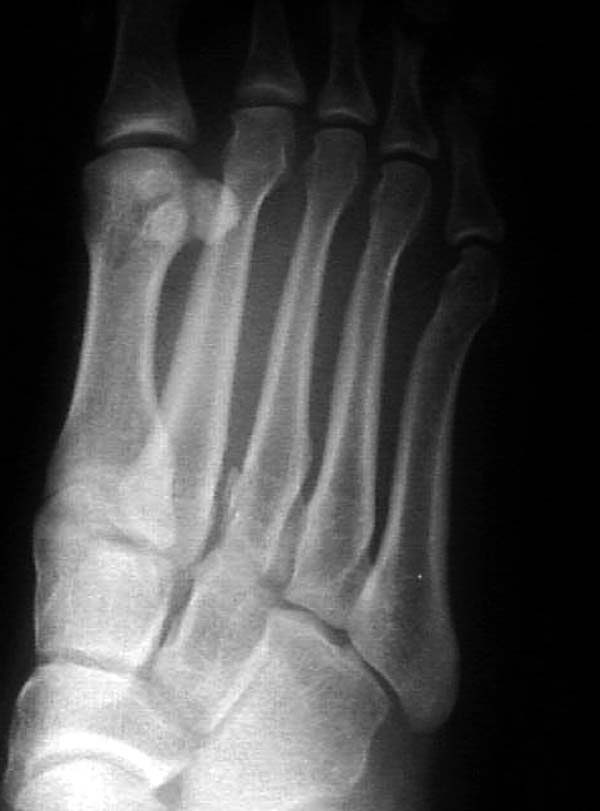

По снимкам нельзя исключить разрыв связки Лисфранка (связки между медиальной клиновидной костью и основанием второй плюсневой). Помогает в диагностике клиника (наличие изолированной гематомы на подошвенной поверхности стопы) и МРТ картина. Если связка повреждена - необходимо оперативное лечение.

по снимкам также нельзя исключить повреждение еще десятка -двух связок. Нормальные снимки.

По первому снимку, не видя больного, мог бы заподозрить перелом основания 3-й плюсневой кости. Поэтому избрал бы тактику консервативного лечения, как при переломе плюсневых костей без смещения!

Здесь КТ и сравнительные снимки стопы под нагрузкой.

Диагностировано повреждение медиальной и латеральной колонны.

Если оперативное лечение - как и каким доступом?